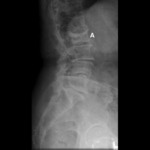

Radiograph of tumor: lymphoma (A) destroying the L5 vertebra

Courtesy of Dr K. Singh; used with permission